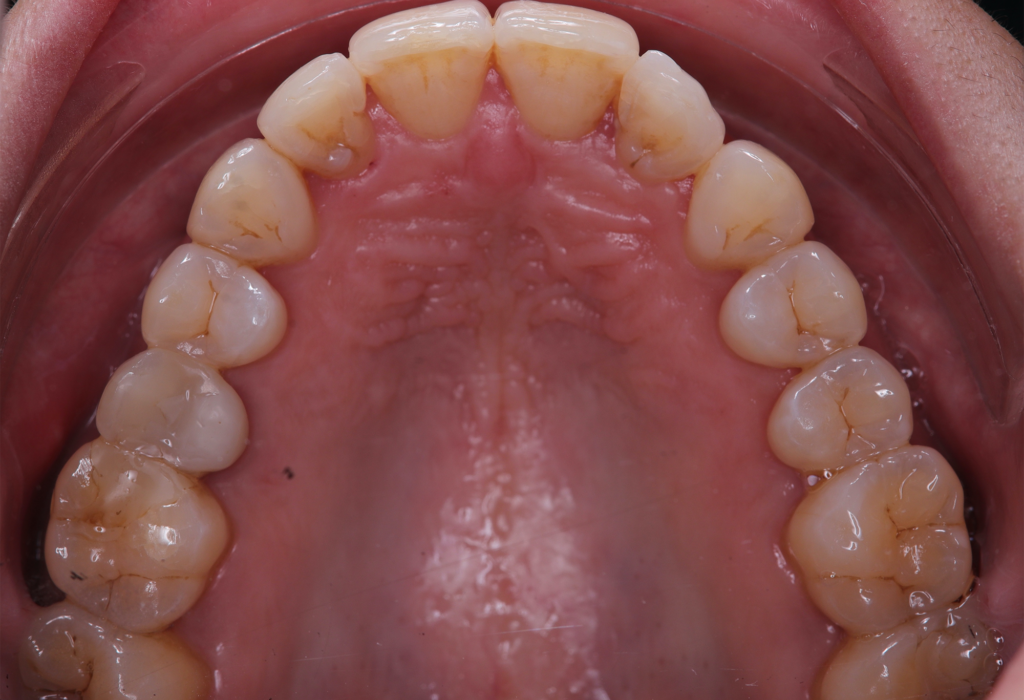

The patient, having completed a periodontal treatment phase, presented with significant aesthetic and functional concerns due to moderate crowding in both arches and a pronounced anterior crossbite. Clinical examination confirmed the need for comprehensive realignment, particularly in the anterior region. Although the patient had a history of periodontal issues, radiographic evaluation showed no signs of active disease. Based on these findings, the treatment plan was designed to carefully modulate orthodontic forces to protect the occlusion and surrounding tissues while addressing the misalignment.

To correct the misalignment and anterior crossbite without compromising tissue stability, a slower orthodontic treatment plan was devised using the Spark Advanced clear aligner system. The initial phase involved 36 aligners designed to gently expand and realign the dental arches, limiting the rate of tooth movement. Strategic interproximal reduction (IPR) was performed in the anterosuperior region (between teeth #21 and #11) to create the necessary space for proper alignment while avoiding excessive loading on the tissues.

To refine the results and enhance aesthetics, a second phase incorporating an additional 17 aligners was introduced. During this refinement stage, careful IPR in the lower arch helped harmonize the midline and achieve a balanced occlusion. Once satisfactory alignment was reached, provisional composite restorations were placed on the upper lateral incisors to aesthetically close any interproximal gaps.